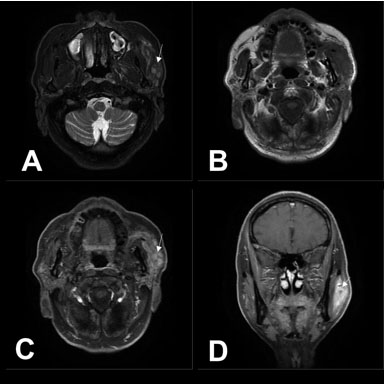

Figure 1: A 62-year-old male with primary parotid squamous cell carcinoma in the left parotid gland. Magnetic resonance images were acquired using a 3.0 T MRI machine. Axial T2WI (A) and T1WI (B) show an irregular mass involving the left parotid gland and masseter muscle, with the tumor showing a slightly low signal and multiple small focal areas of markedly high signal on T2WI (arrow). Enhanced axial (C) and coronal (D) T1WI show inhomogeneous enhancement with necrotic areas in the center (arrow).